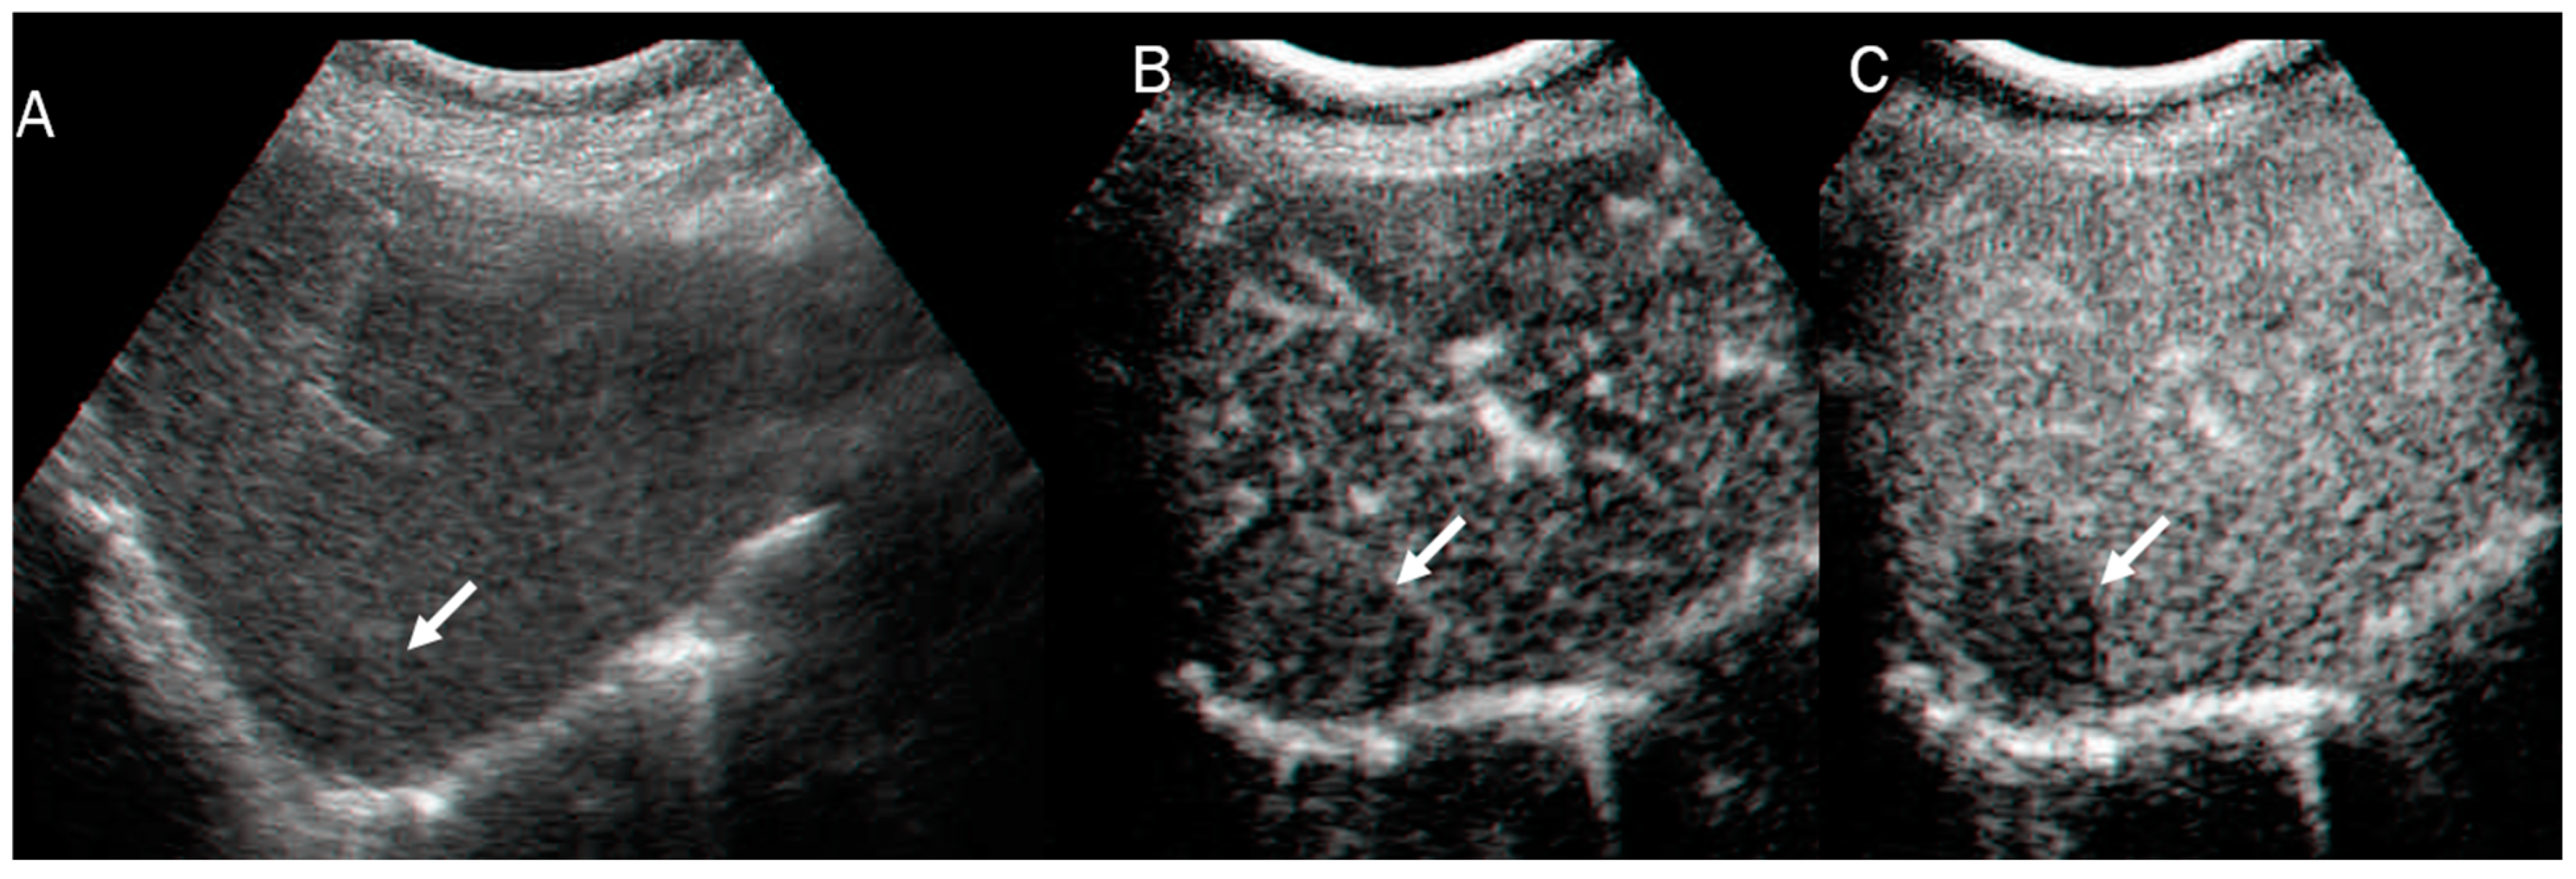

- Peng, Y.; Lin, P.; Wu, L.; Wan, D.; Zhao, Y.; Liang, L.; Ma, X.; Qin, H.; Liu, Y.; Li, X.; et al. Ultrasound-Based Radiomics Analysis for Preoperatively Predicting Different Histopathological Subtypes of Primary Liver Cancer. Front. Oncol. 2020, 10, 1646. [Google Scholar] [CrossRef] [PubMed]

- Ren, S.; Li, Q.; Liu, S.; Qi, Q.; Duan, S.; Mao, B.; Li, X.; Wu, Y.; Zhang, L. Clinical Value of Machine Learning-Based Ultrasomics in Preoperative Differentiation Between Hepatocellular Carcinoma and Intrahepatic Cholangiocarcinoma: A Multicenter Study. Front. Oncol. 2021, 11, 749137. [Google Scholar] [CrossRef]

- Peng, Y.T.; Zhou, C.Y.; Lin, P.; Wen, D.Y.; Wang, X.D.; Zhong, X.Z.; Pan, D.H.; Que, Q.; Li, X.; Chen, L.; et al. Preoperative Ultrasound Radiomics Signatures for Noninvasive Evaluation of Biological Characteristics of Intrahepatic Cholangiocarcinoma. Acad. Radiol. 2020, 27, 785–797. [Google Scholar] [CrossRef]